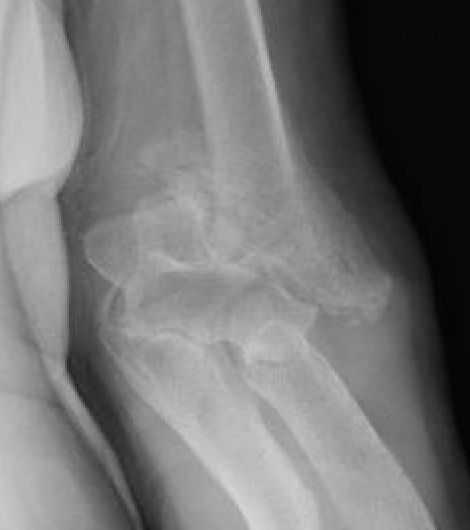

OTA / AO Classification

Type A: Extra-articular fracture

Type B: Partial articular fractures

Lateral condyle Medial condyle

Type C: Complete articular fractures